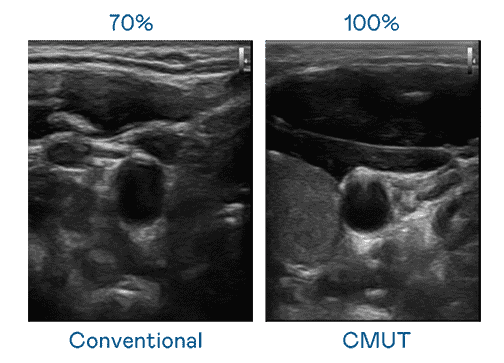

CMUT 技术是一种用电容式微机电元件来产生超音波讯号的技术。。。与传统 PZT 压电式技术相比,,,CMUT 频宽增加 30%,,更宽频的超音波讯号让影像解析度大幅提升,,是实现高影像品质医疗超音波扫描、、、促进精准医疗发展的关键技术。。

大频宽带来超清晰影像

超音波影像的解析度高低,,,,首先取决于探头能发出的讯号频宽。。。z6尊龙 CMUT 可提供高清晰的超音波讯号,,,,提供高频宽、、高灵敏度、、、、影像纹理细节更高的超音波影像,,,协助医护人员缩短影像判读时间及利用精准的医疗影像进行诊断。。。